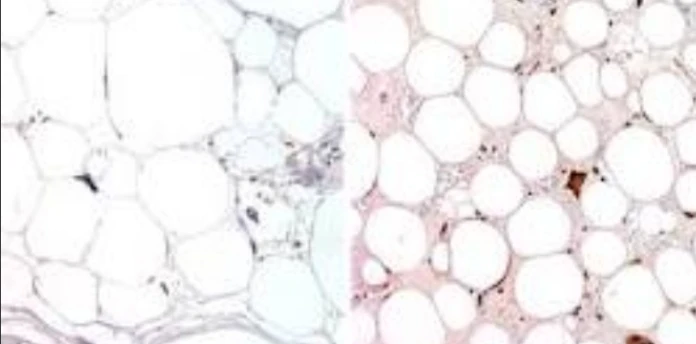

Immunohistochemistry: CDK4

الصورة التوضيحية المرتبطة بهذا التحليل